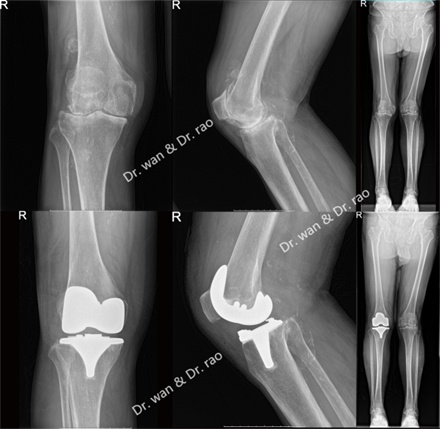

王先生今年84岁,双侧膝关节疼痛难忍10余年。其妻子十年前曾在外院做过膝关节置换手术,由于术后效果并不理想,导致王先生对关节置换手术顾虑重重,甚至对关节置换手术产生心理恐惧。近年来,王先生自觉双侧膝关节疼痛加重,无法下蹲,上下楼梯困难,平地行走疼痛加剧,休息后疼痛无法完全缓解,诊断为骨关节炎膝外翻畸形。虽然王先生有明确的关节置换手术指征,但由于他对关节置换的恐惧心理,只于一年前在外院行膝关节镜手术治疗,术后关节疼痛无法缓解,严重影响日常生活。

近日,王先生终于被女儿说服,在女儿的陪同下,慕名来到同济大学附属同济医院骨科就诊并住院治疗。在骨科关节外科副主任饶志涛的带领下,经过副主任医师万大千周密的检查和关节外科全科病例分析,根据骨科学科带头人程黎明教授《运动骨关节病学》中对骨性膝关节炎的分型介绍,确诊该患者已出现膝关节畸形——膝外翻情况。因此,骨科团队为患者量身定制了手术方案,决定为其进行全膝关节置换术治疗。手术非常顺利,下肢力线和软组织平衡完美恢复,患者术后第一日疼痛明显缓解,即刻下地行走。王先生对关节置换手术疗效和快速康复非常满意,恐惧心里也因此烟消云散。

膝外翻(valgus knee)是退化性骨关节炎中相对少见的下肢畸形,约占10%。它不仅是一种姿态上的畸形,而且也属于一种功能性畸形。表现为双下肢自然伸直或站立时,两侧膝关节向内侧靠拢,而两侧脚跟必须向外分开。双侧发病者称为X形腿,单侧发病者称为K形腿。

正常的膝关节,压力是平均分布在关节面上的。而X型腿的人,由于膝关节外翻,身体重量就过多集中于膝关节外侧关节面上,使关节外侧所受的应力增大,对侧相对减少,同时下肢力线不良,髌骨及股骨之间的摩擦增多,易导致髌骨软化。过度的压力和摩擦力,会导致膝关节外侧软骨面磨损,胫骨平台塌陷,继发骨性关节炎。随着年龄增长,就容易出现关节痛,影响到正常的行走活动。膝外翻的常见原因有三种,一种是小儿的佝偻病,一种是先天的遗传,另外还有一少部分是因为软骨发育障碍、外伤、骨折等引起的后遗症。这种腿部的畸形不仅影响体形与健美,对于人体健康也有较大的影响,对于这种腿形进行矫正,不仅能够增进体形的健美,还可以改善膝关节应力不平衡的状态,缓解患者的病痛。